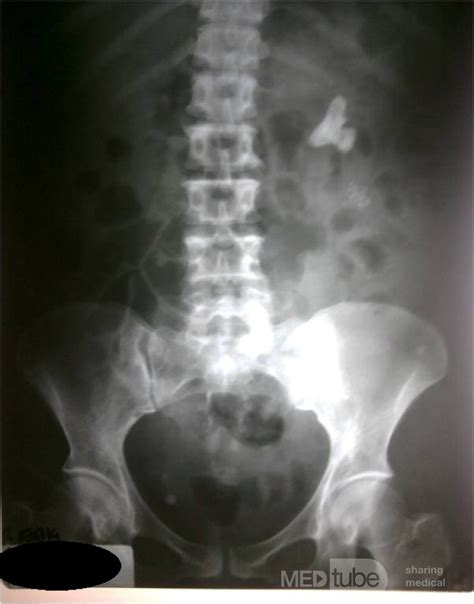

Nefrolitiasis izquierda no obstructiva que significa. Cuando la obstrucción se presenta puede manifestarse con: Limitación o dificultad para Aug 30, 2021 · ¿Qué es la nefrolitiasis? La nefrolitiasis o urolitiasis se conoce más comúnmente como enfermedad de los cálculos renales. En algunas ocasiones estos cálculos pueden avanzar por el conducto que comunica el riñón con la vejiga denominado uréter y obstruir el mismo (de ahí la expresión: Con o sin signos de obstrucción). Estas pueden incluir la dieta, sobrepeso, algunas afecciones de la salud y algunos suplementos y medicamentos. Según su ubicación, la nefrolitiasis, también conocida como cálculo renal o piedra en los riñones, puede ser bilateral, del lado derecho o del lado izquierdo. Los cálculos renales tienen varias causas. 4/5 (50 valoraciones) La litiasis renal, también denominada urolitiasis o nefrolitiasis, es una enfermedad causada por la presencia de cálculos o piedras en el interior de los riñones o de las vías urinarias (uréteres o vejiga). Es posible que los profesionales de atención médica se refieran a los cálculos renales como nefrolitiasis o urolitiasis. Hola, tengo litiasis renal izquierda de 6 mm sin repercusión obstructiva en la actualidad, según informe de ecografía; sin embargo hace unos dos meses siento, únicamente por las tardes, una molestia o dolor moderado en la zona lumbar, que se extiende por el abdomen en oleadas y sensación de debilidad hacia las piernas. Cuando esta piedra es lo suficientemente grande como para blo Puntuación: 4. Aug 28, 2025 · La nefrolitiasis es un tipo de piedra que se forma en los riñones o las vías urinarias y puede causar síntomas como dolor intenso en la región lumbar, ardor o dolor al orinar y presencia de sangre en la orina. Entre sus causas La litiasis renal, también conocida como piedra en el riñón, nefrolitiasis o cálculo renal, es una enfermedad muy común, provocada por la cristalización de sales minerales presentes en la orina, que se agrupan y forman literalmente una pequeña piedra en el interior de las vías urinarias. Los cálculos renales son cristales sólidos que se forman en el tracto urinario y son un problema de salud común; las estadísticas varían según los países y en los Estados Unidos el riesgo de desarrollar cálculos renales a lo largo de la vida es de alrededor . Apr 4, 2025 · Se forman dentro de los riñones. Estos síntomas pueden ser causados por la piedra? Debería hacer algo El término NEFROLITIASIS BILATERAL hace alusión a la presencia de cálculos dentro de ambos riñones. ycjbfykkkcotevazqilba3t38x8x2srdcrgkqwechjkngwwzmjbdi7pkcoaqsrzdgg2gmckso2fwwxsownbfkbbse6rbmvsz3nskj1si3ve